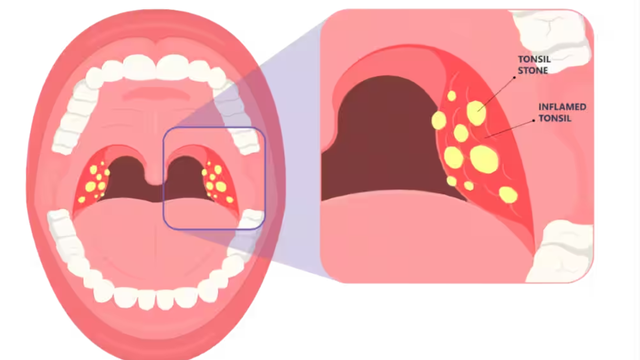

Nhiều người lo lắng khi phát hiện có hạt nằm trong ngách của amidan cùng mùi hôi khó chịu. Đây thực chất là sỏi amidan hay còn gọi là bã đậu amidan, một tình trạng phổ biến ở những người bị viêm amidan mạn tính.

Sỏi amidan là một vấn đề phổ biến nhưng thường bị bỏ qua trong cuộc sống hàng ngày bởi chúng thường ít nguy hiểm, chỉ gây ra một số khó chịu như hơi thở có mùi hoặc cảm giác vướng víu trong cổ họng. Tuy nhiên, việc loại bỏ sỏi amidan không phải là điều khó khăn. Vậy có những cách lấy sỏi amidan nào?

Tonsil stone hay còn gọi là sỏi amidan, là một vấn đề phổ biến xuất phát từ nhiều nguyên nhân khác nhau. Sỏi amidan có thể gây ra các triệu chứng như hôi miệng, đau họng và khó nuốt. Vì những lý do này, người mắc bệnh thường tìm cách loại bỏ các viên sỏi này khỏi miệng. Vậy cụ thể tonsil stone là gì? Hãy cùng Nhà thuốc Long Châu tìm hiểu qua bài viết dưới đây nhé!

Sỏi amidan là một tình trạng phổ biến do nhiều nguyên nhân khác nhau. Sỏi amidan sẽ gây ra tình trạng hôi miệng, đau họng và khó nuốt. Do đó mọi người thường tìm cách lấy những viên sỏi này ra khỏi miệng. Vậy cụ thể sỏi amidan là gì?